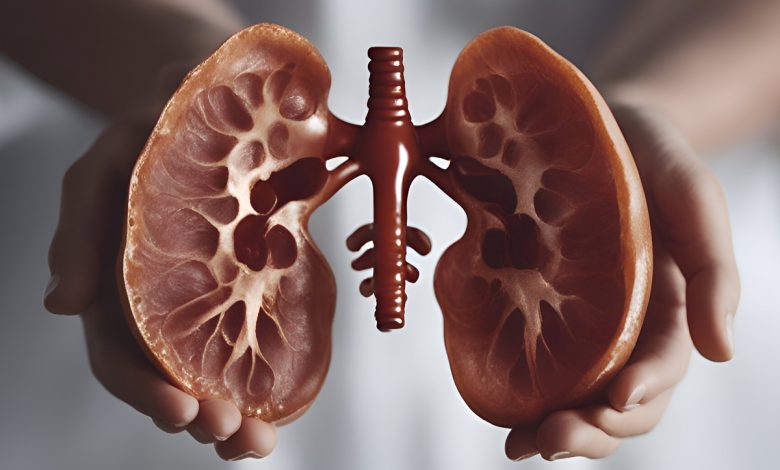

Cada año, el segundo jueves de marzo se conmemora el Día Mundial del Riñón, una iniciativa global para sensibilizar sobre la importancia de la salud renal y prevenir enfermedades que afectan a millones de personas. La Organización Mundial de la Salud (OMS) estima que más del 10% de la población mundial padece algún grado de Enfermedad Renal Crónica (ERC), una afección silenciosa que puede derivar en complicaciones graves si no se detecta y trata a tiempo.

En México, la ERC tiene una alta prevalencia. Según el Global Burden of Disease (GBD) 2021, afecta a 9,184.9 personas por cada 100 mil habitantes. Sin embargo, menos del 10% de los pacientes en etapas tempranas conocen su diagnóstico, lo que retrasa significativamente el inicio del tratamiento y aumenta el riesgo de complicaciones.